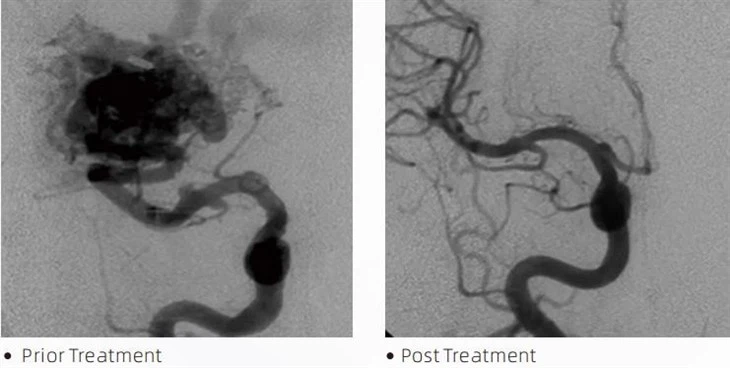

Lava has improved dispersibility and penetration power. They can penetrate deeper into the pathological vessels, accessing even the microvessels at the far end of the lesion. The improved dispersibility and penetration power also mean that the agent fills any irregularities and crevices within the abnormal vessels, resulting in a more complete occlusion.